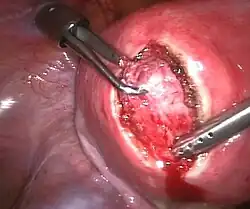

Laparoskopische Myomenukleation

Laparoskopische Myomenukleation -